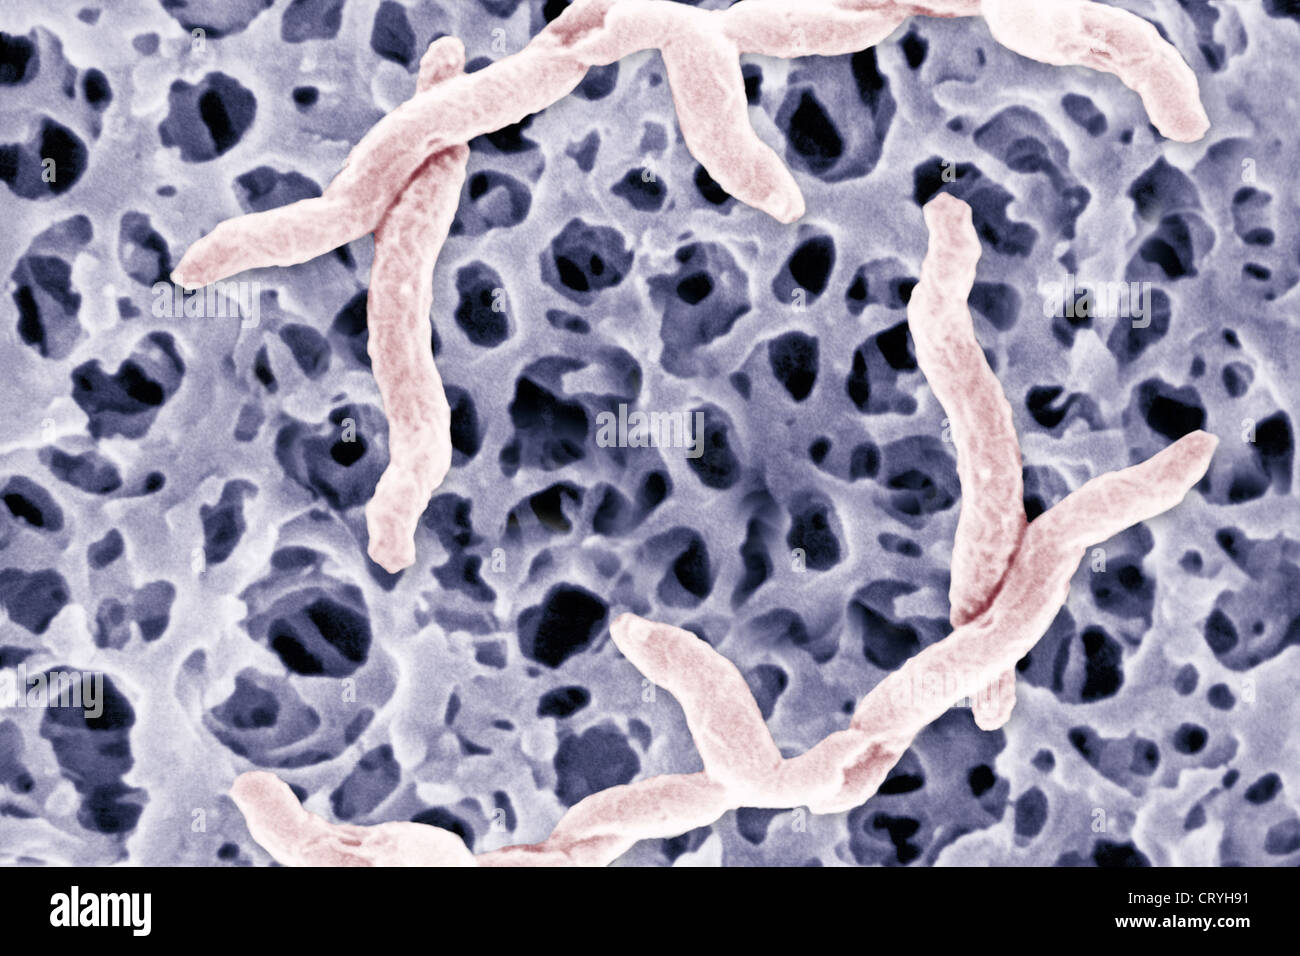

Кампилобактер фетус: патогенез и инфекции